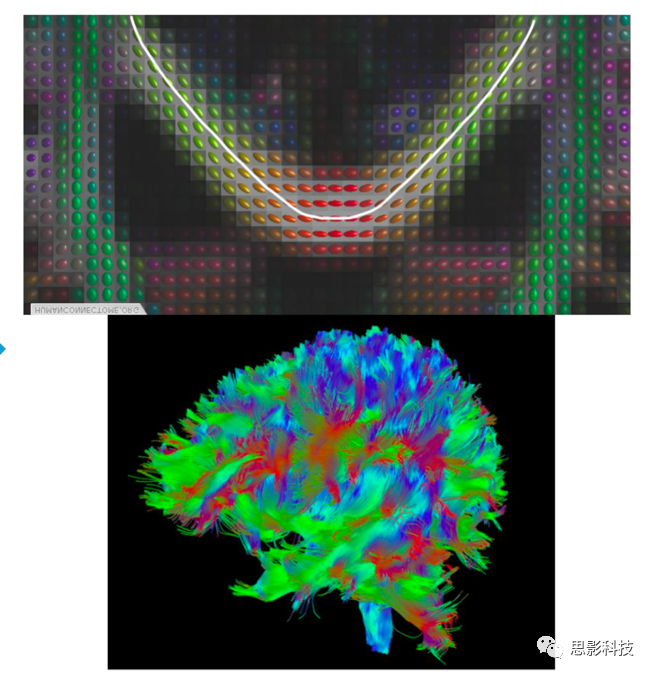

圖例 DTI數(shù)據(jù)處理流程

確定性纖維追蹤主要使用FACT、steamline等追蹤方法根據(jù)張量主方向以及預(yù)設(shè)的偏轉(zhuǎn)角閾值、FA閾值等參數(shù)對(duì)全腦纖維束進(jìn)行構(gòu)建,而后通過(guò)設(shè)定ROI的方式追蹤特定纖維束,并計(jì)算纖維束的數(shù)目、平均FA等相關(guān)指標(biāo)。

圖例:全腦纖維束構(gòu)建